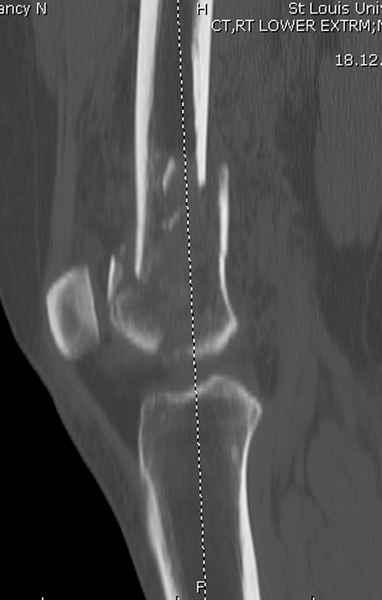

Re: Сегментарный перелом бедра - открыто или закрыто?

При наличии различных имплантов, любые варианты: слева (полу) открытым - мининвазивным, а справа закрытым интрамедуллярным методом, его считаем более чем приемлемым для фиксации данных переломов.

Проксимальная и дистальная блокировка, независимо от техники введения штифта, ретроградно или антеградно, гарантирует сращение сегментарных переломов бедра без укорочения. Штифты диаметром 12 мм с блокировкой сверху и вниз двумя шурупами выдерживают вес 75 кг больного, что позволяет раннюю профилактику контрактур.

Погоня за "красивой рентгенограммой" не всегда оправдана для фиксации кости, где имеется массивное мягкотканое покрытие. Если так уж хочется исправить положение кости, то при наличии ЭОП, большие костные фрагменты могут быть развернуты или приближены к основному фрагменту методом применения Joystick.

Главное в лечении сегментарных переломов - необходима осторожность при рассверливании канала, продвижение гибкого сверло через сегмент проводят без сверления, толканием, а то были случаи, когда весь сегмент крутился вместе со сверлом.